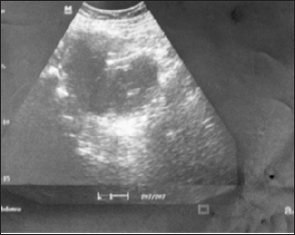

37 yrs old lady with two previous deliveries reported with complaints of pain in lower abdominal area along with difficulty in passing urine of 4 to 5 months duration. Pain was constant but got worse while passing urine, there was increased frequency of micturition and sense of incomplete evacuation but there was no burning while passing urine. She had two living children; both delivered by CS, last CS was performed 8 yrs back. The couple was using male condom as a method of contraception. Her menstrual cycles were absent for the last six to seven months but occasionally she had complained of altered blood stained vaginal discharge. General and systemic examination was essentially normal. Abdominal examination revealed a lump corresponding to 22 weeks size of pregnancy (Figure 1). The mass was firm to cystic in consistency. On internal examination the cervix and uterus could not be felt but a large mass was felt in the vagina, continuous with abdominal mass; whose mobility was restricted.

Figure 1: Large lower abdominal mass arising from pelvis.